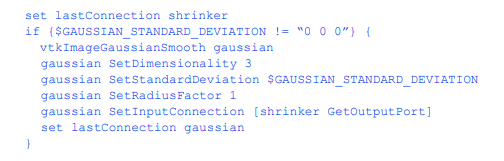

平滑体积数据

到目前为止,除非我们重新采样了数据,否则所选组织的体积被标记为255像素,其他地方为0。如果我们不模糊它,这个“二进制”体积就会产生台阶状的表面。在这个过滤器中指定的高斯核完成了我们提取表面所需的平滑。平滑量由12.2从分段卷数据创建模型451 GAUSSIAN_STANDARD_DEVIATION控制,可以为卷数据的每个轴独立指定。我们只在需要平滑时运行这个过滤器,

生成的三角形